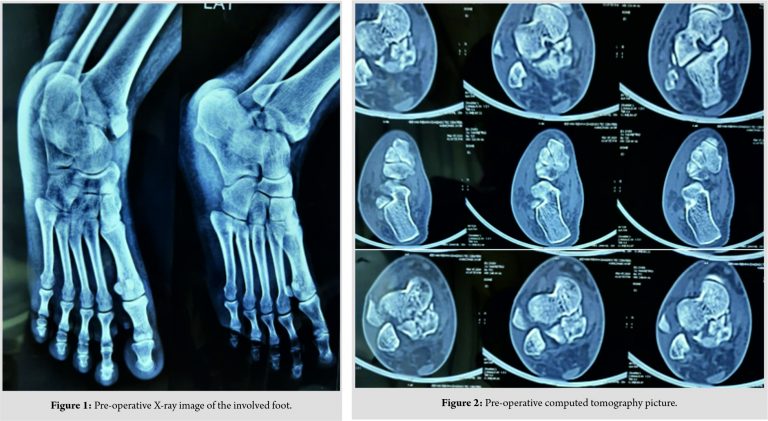

A 30-year-old female presented to our hospital with complaints of pain and swelling over the right ankle joint with difficulty in bearing weight (injury hospital duration of 36 h) following a motor vehicle accident. According to history, the mechanism of injury was axial compression with the supination of the ankle. Initially, the patient was managed with analgesics for pain and trial of closed reduction of fracture followed with short leg cast somewhere else. Then, the patient was referred to our hospital for further management. On examination, there was swelling of the left ankle and foot, associated with no external injury noted; however, the skin over ankle was ecchymosed over medial malleolus. No neurovascular deficit was found. Radiographs of the ankle were taken in anteroposterior and lateral view (Fig. 1), which showed talar body fracture of type 2 Sneppen (classification) with an ipsilateral medial malleolar fracture.

Computed tomography was done to the proper classification of fracture and pre-operative management planning (Fig. 2). An attempt to closed reduction was done in our hospital but was unsuccessful.